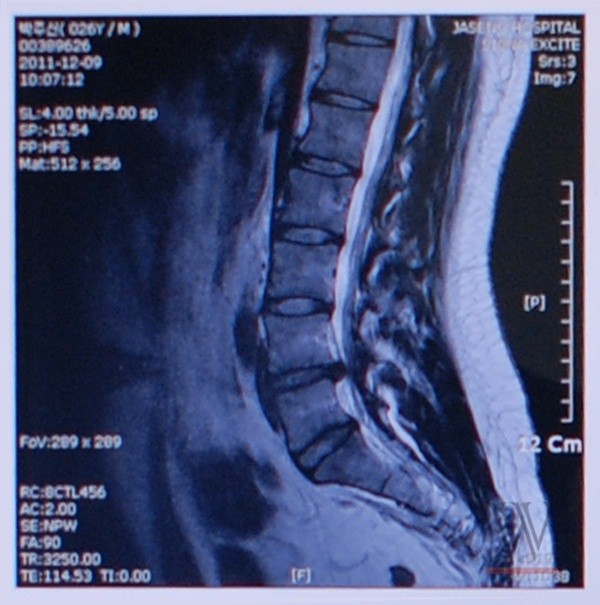

박원순 아들의 병역의혹은 아들이 공개 身檢에서 MRI사진을 한 번 더 찍고 디스크 질환이 있다는 사실만 알리면 끝나는 문제다.

- ▲ 문제의 MRI사진ⓒ

-박주신氏처럼 한방병원(자생한방병원)에서 척추 MRI사진을 찍고 다른 병원에 가서 진단서를 받는 경우는 매우 드문 케이스로 알려져 있는데?

“드문 게 아니고 작년 한 해 통틀어 그런 사례가 없는 걸로 알고 있다. 박원순은 항상 그런 식이었다. 딸의 법대 轉科 문제도 서울대 역사상 최초였다. 아들의 경우도 마찬가지인데, 한방병원에서 MRI찍어서 혜민병원에서 진단서를 받는다는 것은 있을 수 없는 일이다. 병사용 진단서 발급현황을 병무청에서 받아 보았다. 박원순 아들과 같은 케이스는 진단서 효력 자체를 거의 인정하지 않는다. 이런 일은 거의 없다.”